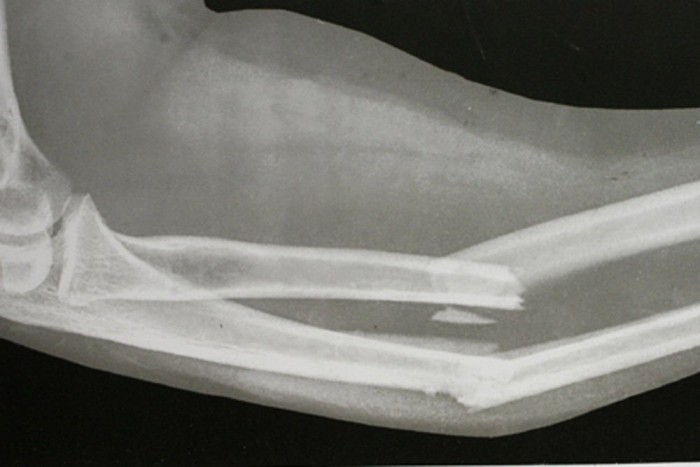

Ütközéskor a pedálok eltörik a sarokcsontot, a bokát, az alsó lábszárat, a szerelvényfal pedig roncsolja a térdízületet, gyakran szilánkosra törik a sípcsont feje, aztán ahogy az energia halad tovább, csípőficam, a medencevápának törése, sőt még az ágyéki gerinc törése is bekövetkezhet – osztotta meg tapasztalatait Detre főorvos úr. Az öv ugyan megfogja a felsőtestet, de a fej így is nekicsapódik a kormánynak, és arccsonttörést, homloktörést, és ezzel együtt agyi traumát okozhat.